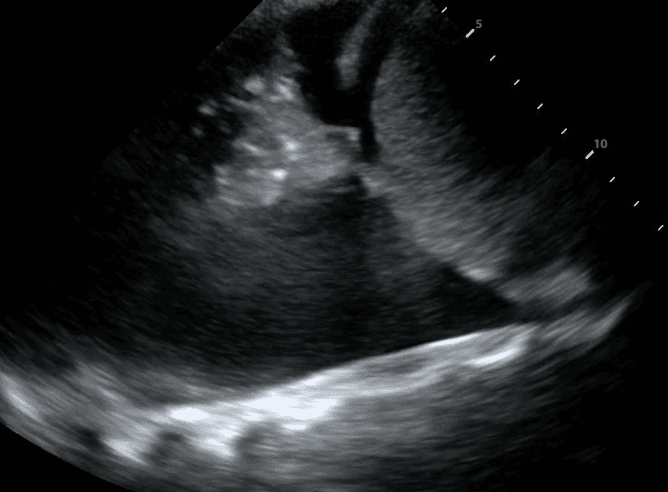

Secondly, you will see a consolidated lung sitting in the effusion. Please refer to our post on consolidations to learn what consolidated lung looks like. If the effusion is large, the consolidated lung will appear to float in the effusion - resembling a jellyfish swimming in the ocean. This is referred to as the “jellyfish sign.”

Estimating the size of a pleural effusion can help determine if, when and where the effusion can be drained. Effusion size may be qualitatively classified as small, medium or large. If there is a “jellyfish sign,” the effusion is at least moderate to large in size.